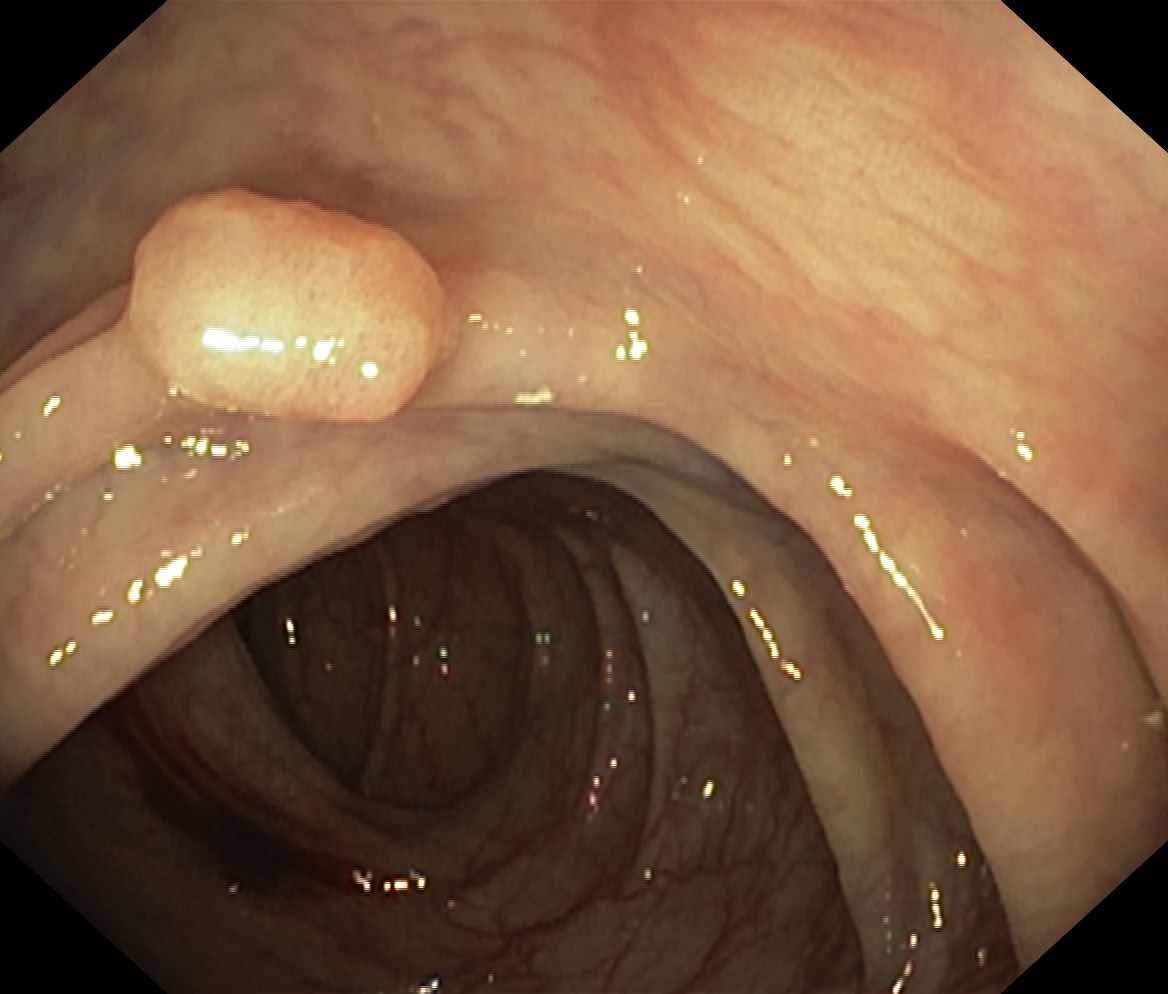

Polipy